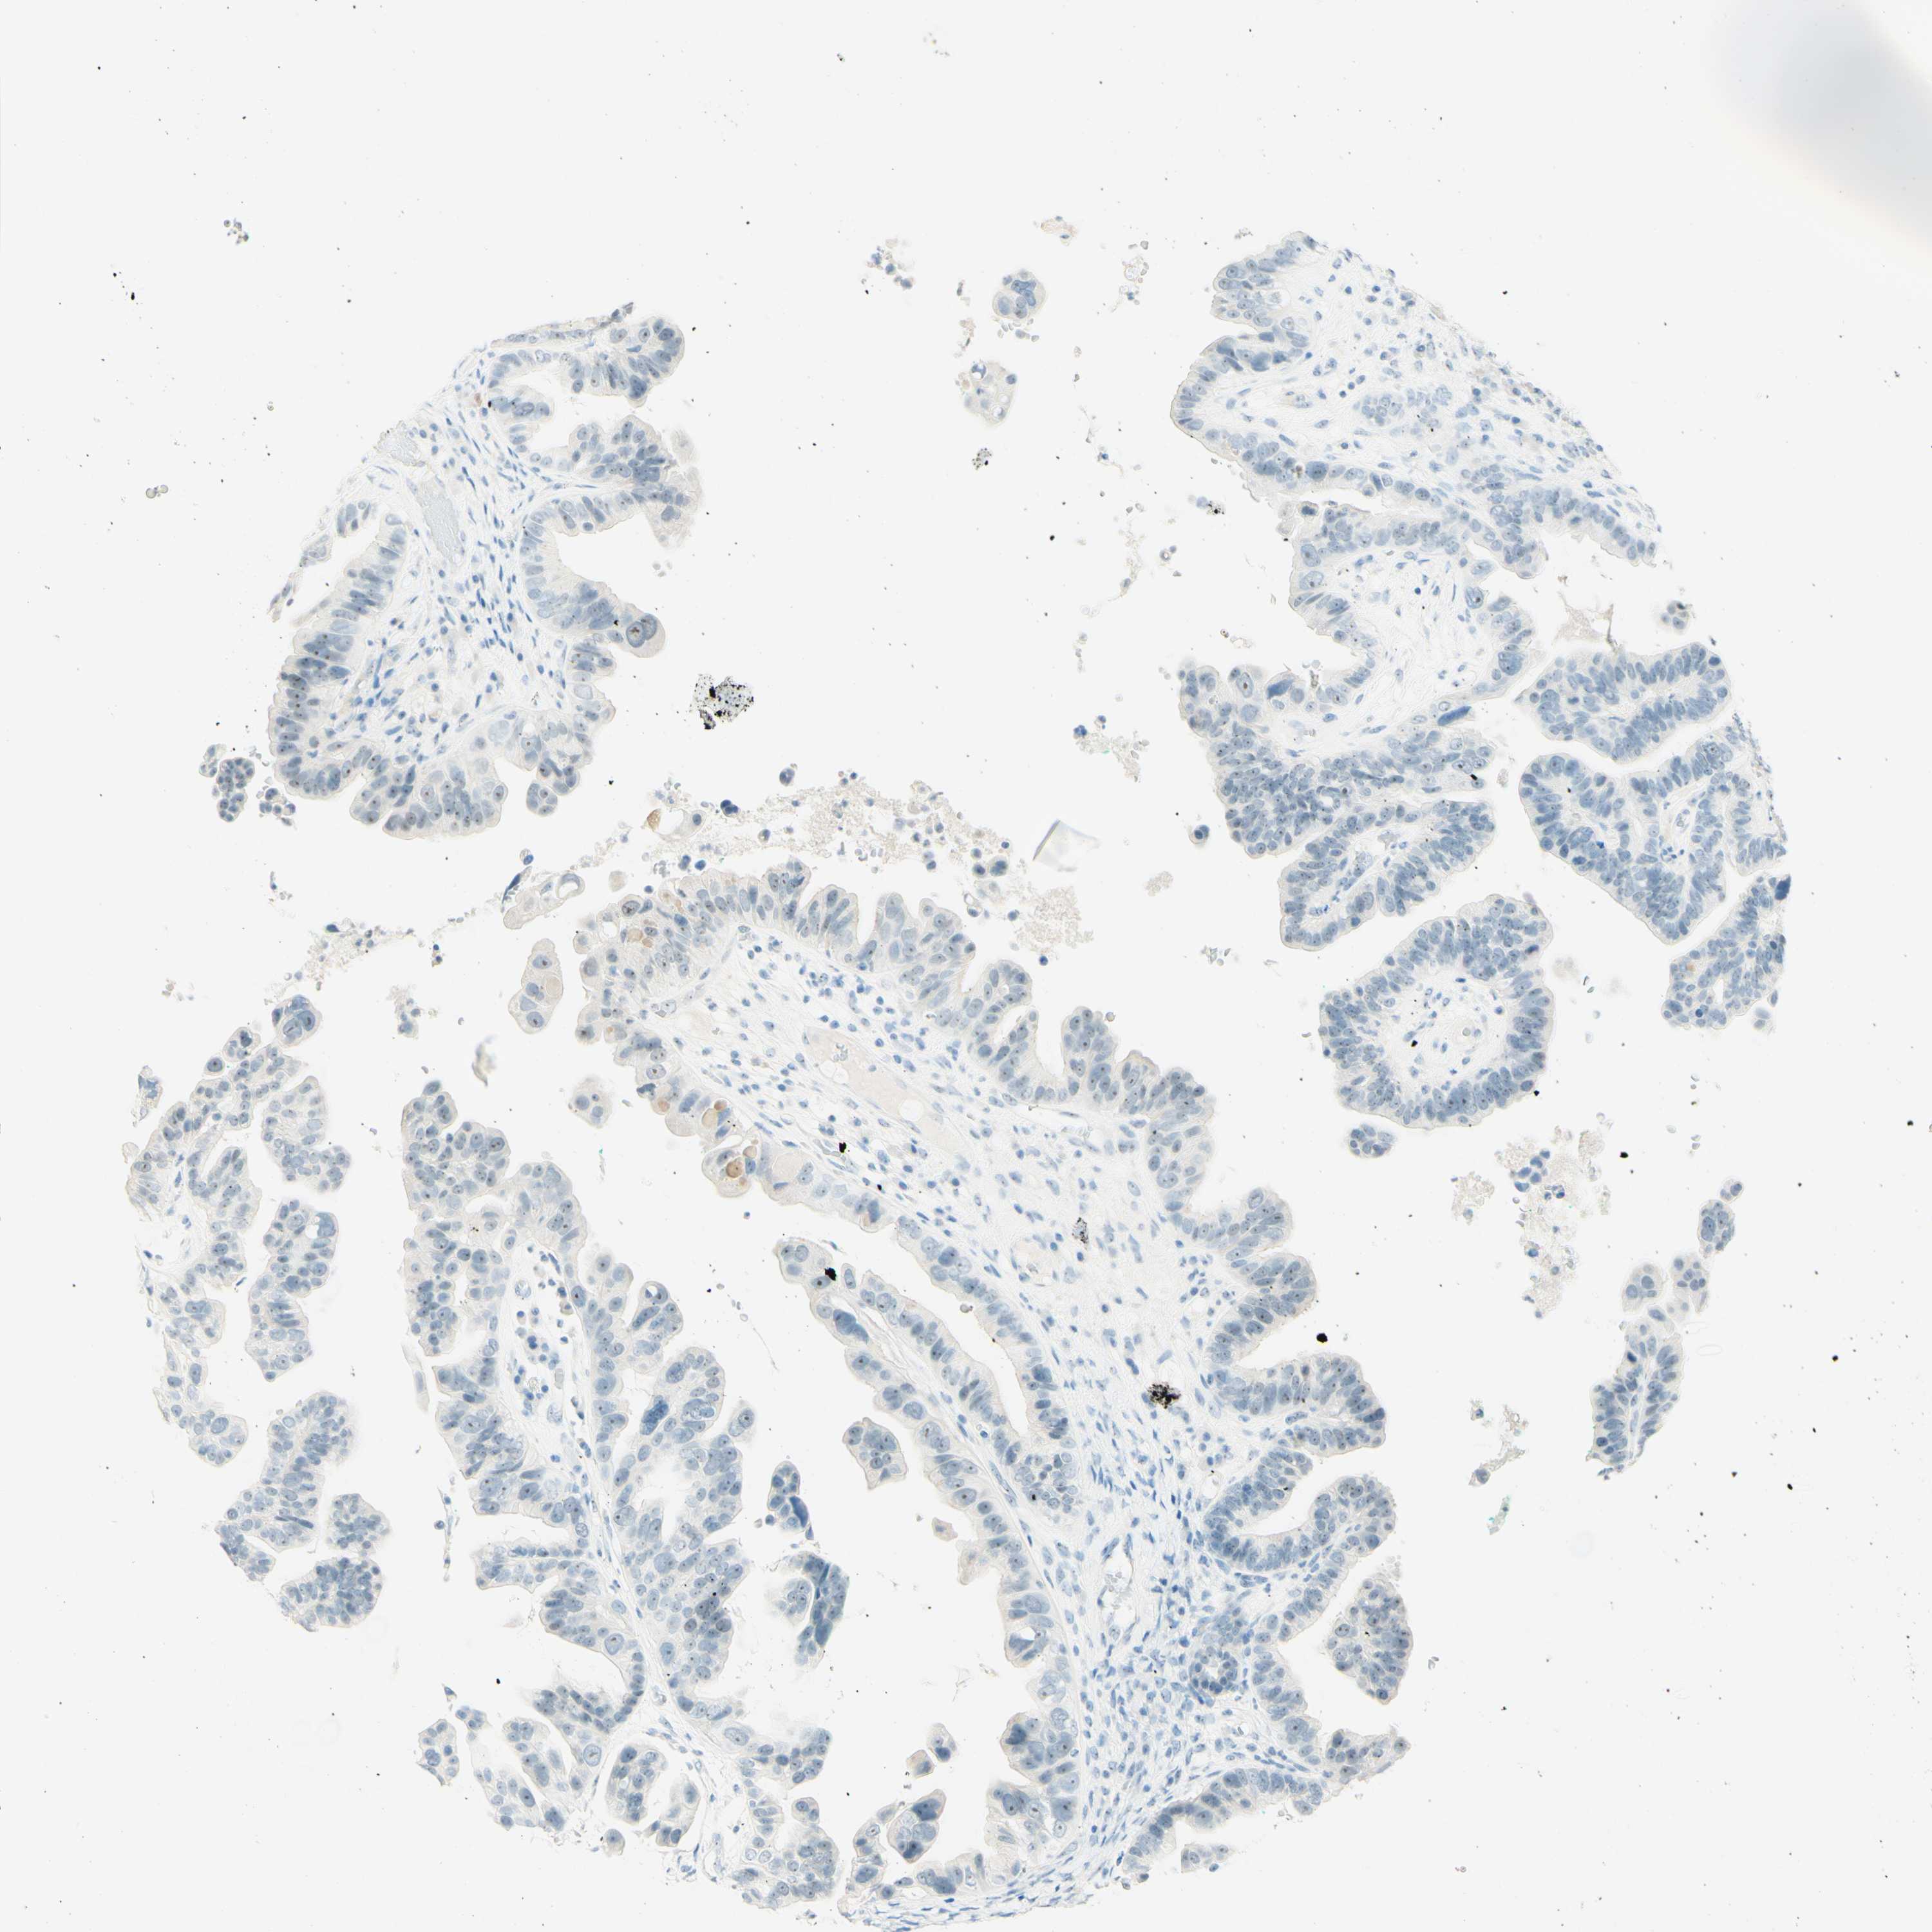

OVARIAN CANCER - Protein expressioni

A mouse-over function shows sample information and annotation data. Click on an image to view it in a full screen mode. Samples can be filtered based on level of antibody staining by selecting one or several of the following categories: high, medium, low and not detected. The assay and annotation is described here.

Note that samples used for immunohistochemistry by the Human Protein Atlas do not correspond to samples in the TCGA dataset.

Antibody stainingi

Antibody staining in the annotated cell types in the current human tissue is reported as not detected, low, medium, or high, based on conventional immunohistochemistry profiling in selected tissues. This score is based on the combination of the staining intensity and fraction of stained cells.

Each image is clickable and will lead to virtual microscopy that enables deeper exploration of all samples and also displays staining intensity scores, fraction scores and subcellular localization as well as patient and tissue information for each sample.

Antibody HPA011284

Antibody CAB026403

Cystadenocarcinoma, serous, NOS

Carcinoma, endometroid

Cystadenocarcinoma, mucinous, NOS

Carcinoma, NOS